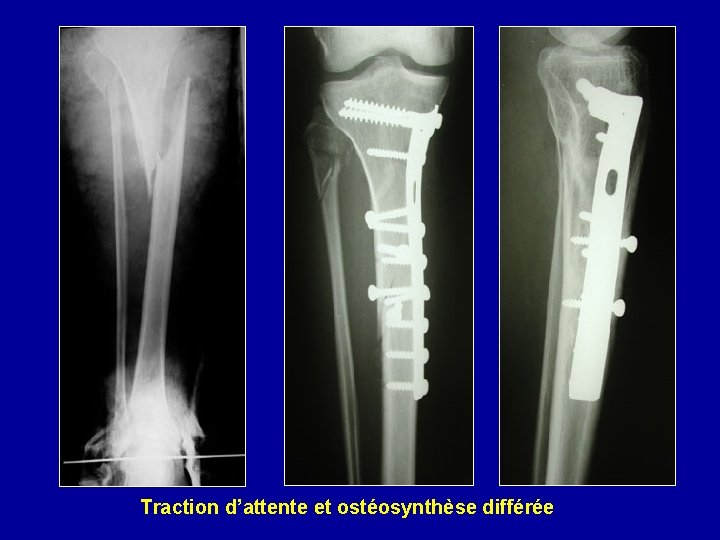

Traction d’attente et ostéosynthèse différée

Photo J. Chouteau